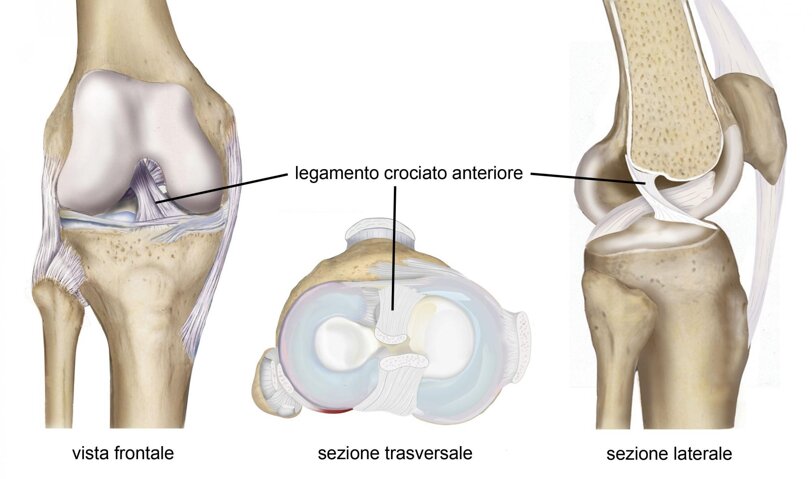

Il Legamento crociato anteriore (LCA) è il principale stabilizzatore statico del ginocchio e costituisce insieme al legamento crociato posteriore il pivot centrale. E’ una struttura intra-articolare, la cui origine femorale è da ricercare sulla superficie mediale del condilo femorale esterno nella porzione posteriore della gola intercondiloidea. Il legamento decorre poi anteriormente, distalmente e medialmente verso la sua origine tibiale. E’ costituito da due fasci: antero-mediale e postero-laterale.